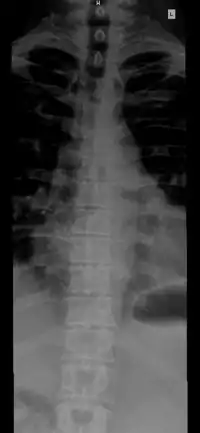

The vertebral column, also known as the backbone or spine, is part of the axial skeleton. The vertebral column is the defining characteristic of a vertebrate in which the notochord (a flexible rod of uniform composition) found in all chordates has been replaced by a segmented series of bone: vertebrae separated by intervertebral discs.[1] Individual vertebrae are named according to their region and position, and can be used as anatomical landmarks in order to guide procedures such as lumbar punctures. The vertebral column houses the spinal canal, a cavity that encloses and protects the spinal cord.

Structure

The number of vertebrae in a region can vary but overall the number remains the same. In a human vertebral column, there are normally 33 vertebrae.[3] The upper 24 pre-sacral vertebrae are articulating and separated from each other by intervertebral discs, and the lower nine are fused in adults, five in the sacrum and four in the coccyx, or tailbone. The articulating vertebrae are named according to their region of the spine. There are seven cervical vertebrae, twelve thoracic vertebrae and five lumbar vertebrae. The number of those in the cervical region, however, is only rarely changed,[4] while that in the coccygeal region varies most.[5] One study of 908 human adults found 43 individuals with 23 pre-sacral vertebrae (4.7%), 826 individuals with 24 pre-sacral vertebrae (91%), and 39 with 25 pre-sacral vertebrae (4.3%).[6]

The vertebrae in the human vertebral column are divided into different regions, which correspond to the curves of the spinal column. The articulating vertebrae are named according to their region of the spine. Vertebrae in these regions are essentially alike, with minor variation. These regions are called the cervical spine, thoracic spine, lumbar spine, sacrum, and coccyx. There are seven cervical vertebrae, twelve thoracic vertebrae, and five lumbar vertebrae.

Individual vertebrae are named according to their region and position. From top to bottom, the vertebrae are:

- Cervical spine: 7 vertebrae (C1–C7)

- Thoracic spine: 12 vertebrae (T1–T12)

- Lumbar spine: 5 vertebrae (L1–L5)

- Sacrum: 5 (fused) vertebrae (S1–S5)

- Coccyx: 4 (3–5) (fused) vertebrae (Tailbone)